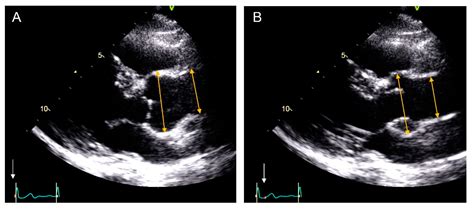

Diagnostic Guidelines for Normal Aorta Diameter

Determining the Normal Aorta Diameter is typically done using non-invasive imaging technologies like Echocardiography, Computed Tomography (CT) scans, or Magnetic Resonance Imaging (MRI). Generally, a measurement in the abdominal aorta that exceeds 3.0 cm is considered the upper limit of normal, whereas anything above 5.0 cm in the thoracic region often triggers clinical concern.